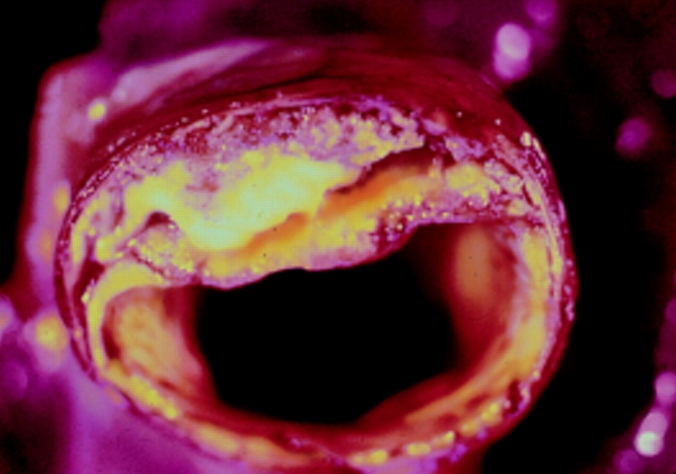

Athersclerosis, a slice of an artery; with yellow

paque encapsulated in middle of wall

Similar statement from a journal article:  Atherosclerosis develops over the course of 50 years, beginning in the early teenage years. The causes of this process appear to be lipid retention, oxidation, and modification, which provoke chronic inflammation at susceptible sites in the walls of all major conduit arteries. Initial fatty streaks evolve into fibrous plaques, some of which develop into forms that are vulnerable to rupture, causing thrombosis or stenosis. Erosion of the surfaces of some plaques and rupture of a plaque’s calcific nodule into the artery lumen also may trigger thrombosis. The process of plaque development is the same regardless of race/ethnicity, sex, or geographic location, apparently worldwide. However, the rate of development is faster in patients with risk factors such as hypertension, tobacco smoking, diabetes mellitus, obesity, and genetic predisposition.  At ftp://82.239.144.183/bibli/-%20Revue%20Articles%20FB/Biblio%20090410/110.0901-Pathology%20of%20AthS,%20Plaque%20development%20and%20plaque%20responses%20to%20medical%20treatment%20(Insull,%20Am%20J%20Med).pdf